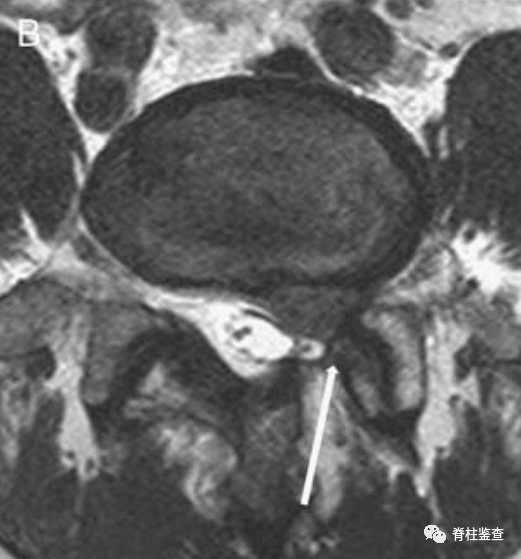

完全减压后,可以看到神经根的外侧和腹侧部分(白色↓),附着在硬膜上的瘢痕组织未被剥离(黑色↓)。通过纤维环缺损 (双白↓)进一步取出椎间盘。

术后第1天显示,椎间盘充分移除;MR图像中的瘢痕组织限制了硬膜囊的充分扩张(白色↓)。